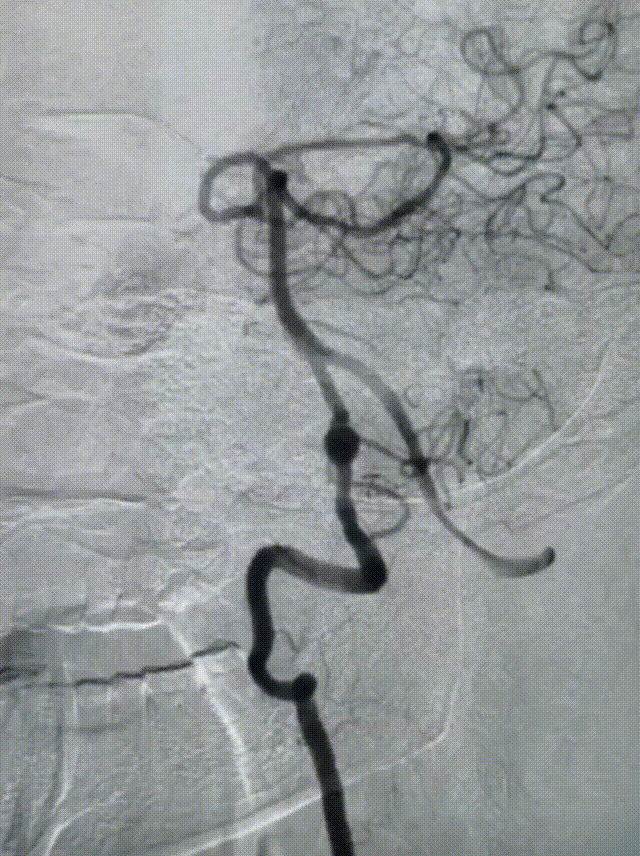

术前影像学检查:全脑血管造影检查提示右侧椎动脉V5段(颅内段)夹层动脉瘤。

动脉瘤大小约5.45mm×7.31mm,动脉瘤远端椎动脉汇合前管径约2.77mm,动脉瘤近端V4段管径约3.80mm,V5段全长约35mm,对侧椎动脉正常。

测量数据